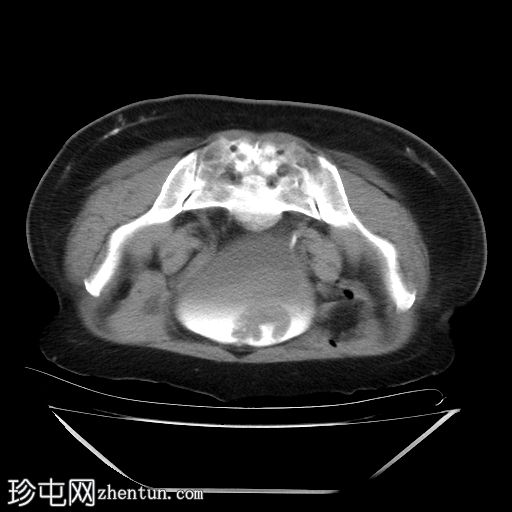

俯卧位轴位扫描

延迟期

4.jpg

采用俯卧位CT扫描显示病变活动度。

膀胱血肿常被误诊肿瘤性肿块。俯卧位是区分可移动血块和固定于膀胱壁的肿瘤的关键操作。这种简便的技术,结合无对比剂增强,可提供强有力的非侵入性证据,排除肿瘤性病变。